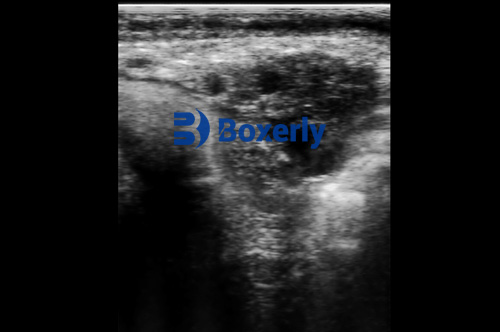

Veterinary ultrasound, particularly B-mode real-time imaging, allows for non-invasive, accurate, and immediate observation of the internal reproductive structures of cattle. This includes the uterus, ovaries, follicles, corpus luteum (CL), and early pregnancy status. Compared to traditional rectal palpation, ultrasound imaging offers significantly better sensitivity and specificity, and it enables the detection of small ovarian structures that might otherwise go unnoticed.

By far the most common method used worldwide, the transrectal approach involves inserting a short veterinary ultrasound probe into the rectum. The probe is positioned against the rectal wall, which lies adjacent to the uterus and ovaries, allowing the operator to scan these structures through the intestinal wall.

Allows detailed observation of follicles, CL development, and pregnancy status

Suitable for early detection of ovarian disorders and silent estrus